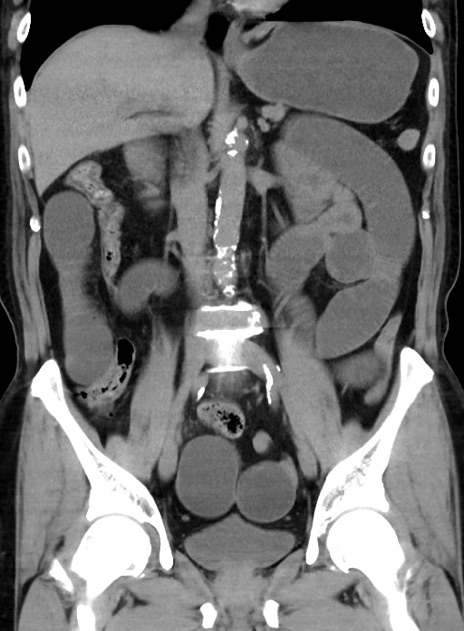

症例38(冠状断像)

【症例】70歳代 男性

【主訴】腹痛・嘔吐

【現病歴】昨晩より、嘔吐・腹痛あり。今朝になっても嘔吐あり。来院。

【既往歴】心臓バイパス手術、開腹胆摘、腸閉塞

【身体所見】BP 107/71mmHg、HR 116/min、腹部:平坦、軟、下腹部に軽度圧痛あり。反跳痛なし。

【データ】WBC 15100、CRP 0.32